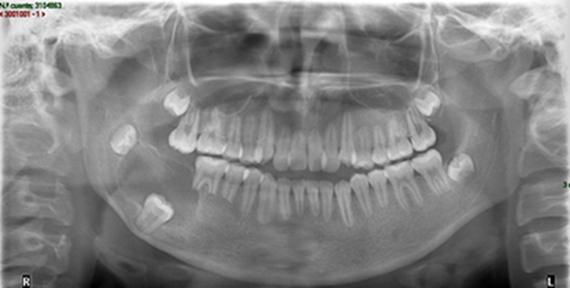

Paciente masculino de 10 años de edad refirió haber tenido un golpe hace 5 días aproximadamente. No refirió antecedentes patológicos.

A la exploración física refirió dolor a la percusión y palpación en la pieza 2.1, radiográficamente se observó fractura horizontal en el tercio medio de la raíz (Fig.1), por lo que se decidió ferulizar de la pieza 1.2 a 2.2 (Fig.2).

Fig. 1

Fig. 2

El paciente regresó a los 15 días, se le retiró la férula y se inició el tratamiento de endodoncia anestesiando al paciente, se colocó aislamiento absoluto para posteriormente realizar el acceso a la cámara pulpar con una fresa bola #4 de carburo de tallo largo, se tomó la longitud de trabajo con una lima #20, guiándonos con el localizador de ápices (Root ZX II), la cual fue de 16mm, tomando como punto de referencia el borde incisal (Fig.3).

Se instrumentó hasta la cavometría obtenida desde el borde incisal hasta la línea de la fractura con limas manuales. Se conformó el conducto hasta la lima #70 Flex-R. Se colocó Ultracal (hidróxido de calcio) como medicamento intra-conducto. Se colocó Cavit (ionómero de vidrio) como obturación provisional (Fig.4). Se citó al paciente 7 días posteriores.

Fig. 3

Fig. 4

En la siguiente cita se retiró el Ionómero de Vidrio y se irrigó con vibración ultrasónica pasiva para remover el hidróxido de calcio de las paredes dentinarias. Se secó el conducto con puntas de papel estériles.

Se obturó el conducto colocando un tapón de MTA (agregado de trióxido mineral) hasta el nivel de la fractura, llevando el material con los empacadores de Schilder 3/5 hasta el tope indicado, posteriormente se selló la parte cameral con Ionómero de Vidrio como obturación temporal (Fig.5).

Fig. 5